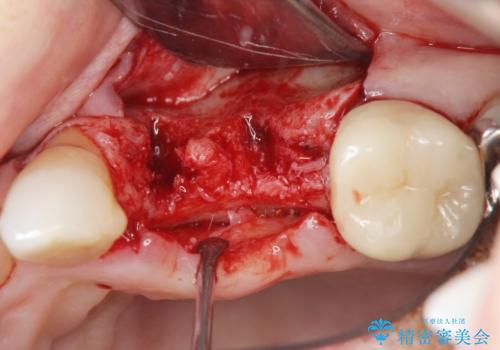

抜去後の補綴治療は長いブリッジではなくインプラント治療を希望されましたが、穿孔・破折による周囲の骨吸収をリカバリーすべく骨の造成を伴うインプラント治療を計画します。

インプラント治療を行うにはインプラント周囲に十分な骨の幅・高さが必要です。

今回はが原因で失われてしまった骨の幅を回復することで長期的な予後を見込めるインプラント治療を行うことができました。